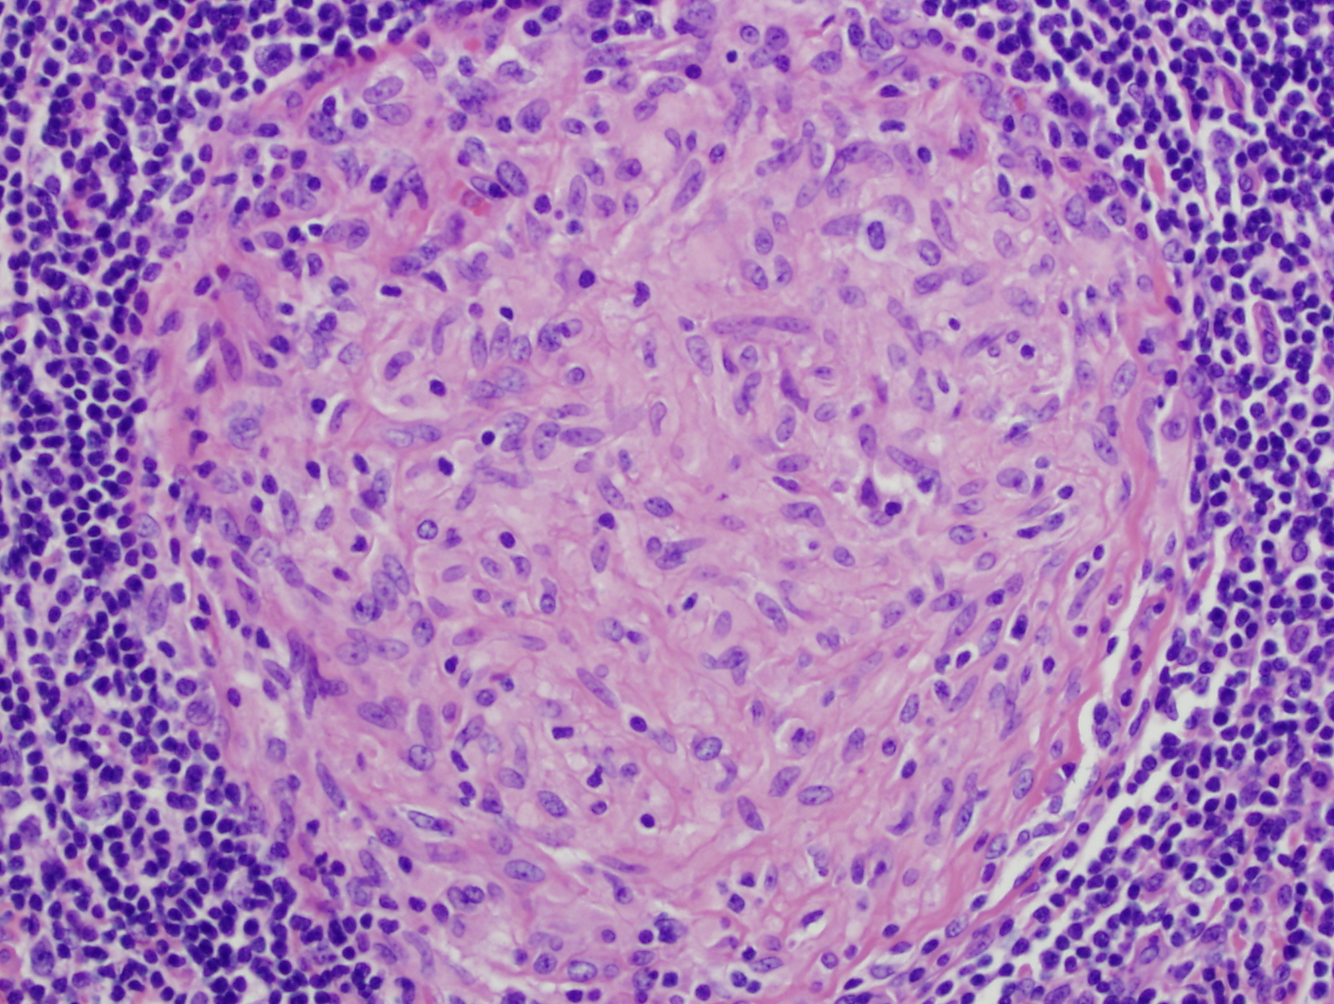

What would you see microscopically in someone with Crohn’s disease?

Granuloma Formation

Central granuloma with epithelioid macrophages